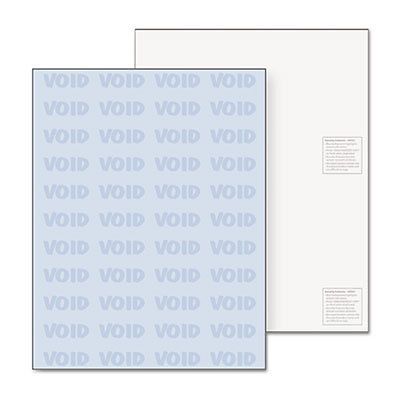

DocuGard Security Paper, Blue, 8-1/2 x 11, 500/Ream, Sold as 1 Ream